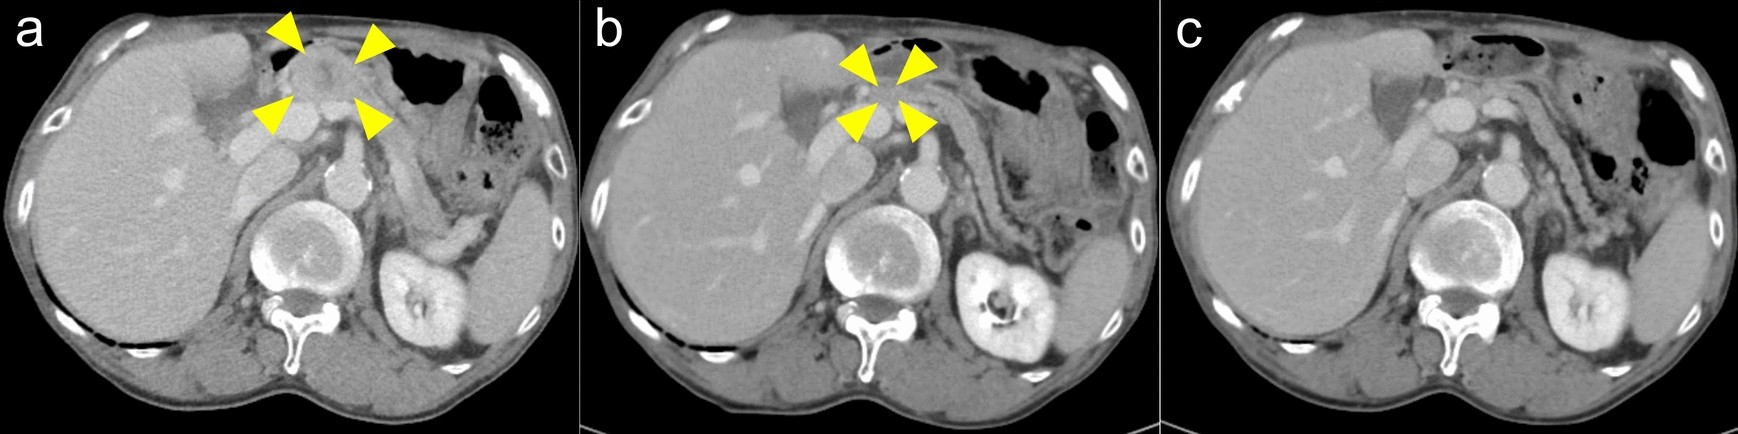

Fig.2

Representative images of the tumor before and during pembrolizumab monotherapy in a patient with pancreatic metastasis of salivary duct carcinoma. (a) Pre-treatment of the patient with pancreatic metastasis. (b) Tumor shrinkage observed 63 days after the initiation of pembrolizumab monotherapy. (c) Tumor disappeared 154 days after the initiation of pembrolizumab monotherapy.